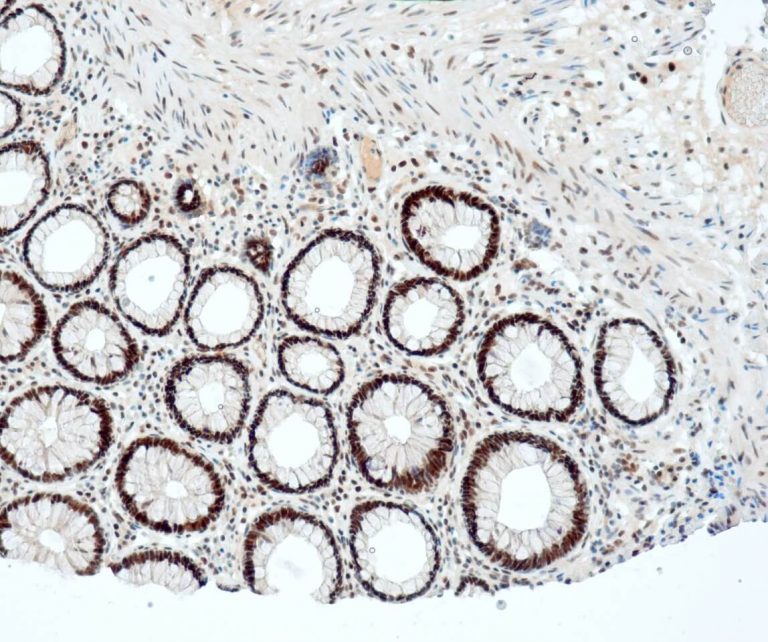

Gastrointestinal (GI) Pathology

General Marker